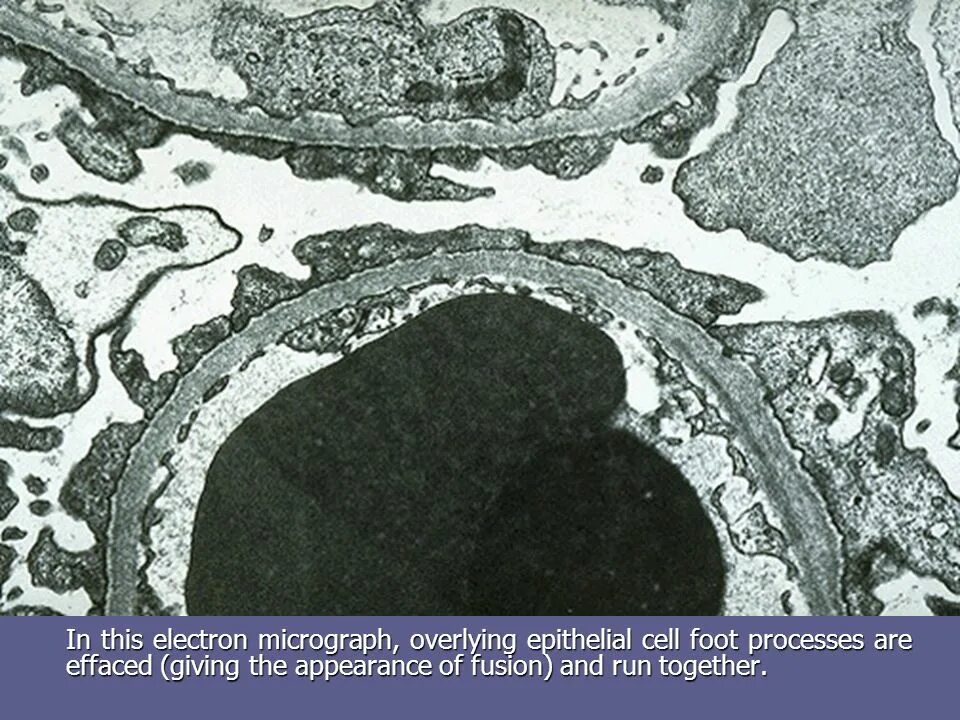

Электронно плотный